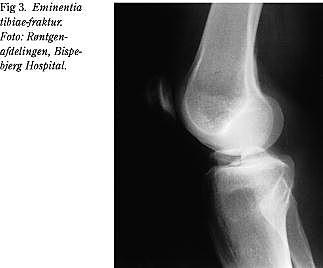

• afrivning af det forreste korsbånd med et knoglestykke fra eminentia tibiae (Fig. 3),

Hos ca. 5% (og hyppigere hos børn) med akut forreste korsbåndsinstabilitet er korsbåndet ikke revet over, men eminentia tibia, som korsbåndet hæfter på, er afrevet (Fig. 3). Ved akut osteosyntese af eminentia kan korsbåndsstabiliteten reetableres i langt de fleste tilfælde.